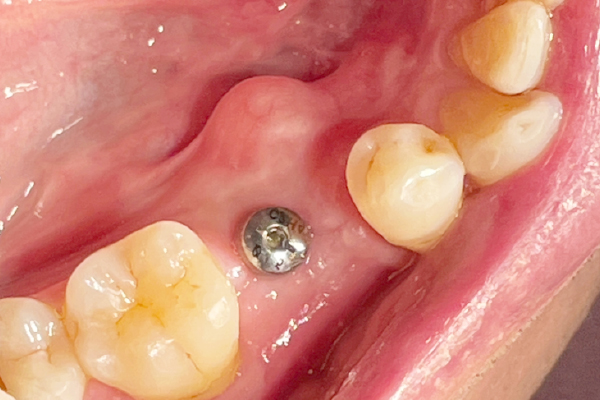

CASE2

インプラントを用いた虫歯治療

| 主訴 | 欠損部分のインプラント埋入 |

|---|---|

| 治療期間 | 3ヶ月(治療回数3回) |

| 治療費 | インプラント1本 330,000円〜385,000円(税込) デンタルローンで月3,000円から始められます |

| 治療の リスク | 治療には神経の治療や抜歯が必要な場合があります。 虫歯や歯周病を防ぐ為に、定期検診にご来院いただきます。 |